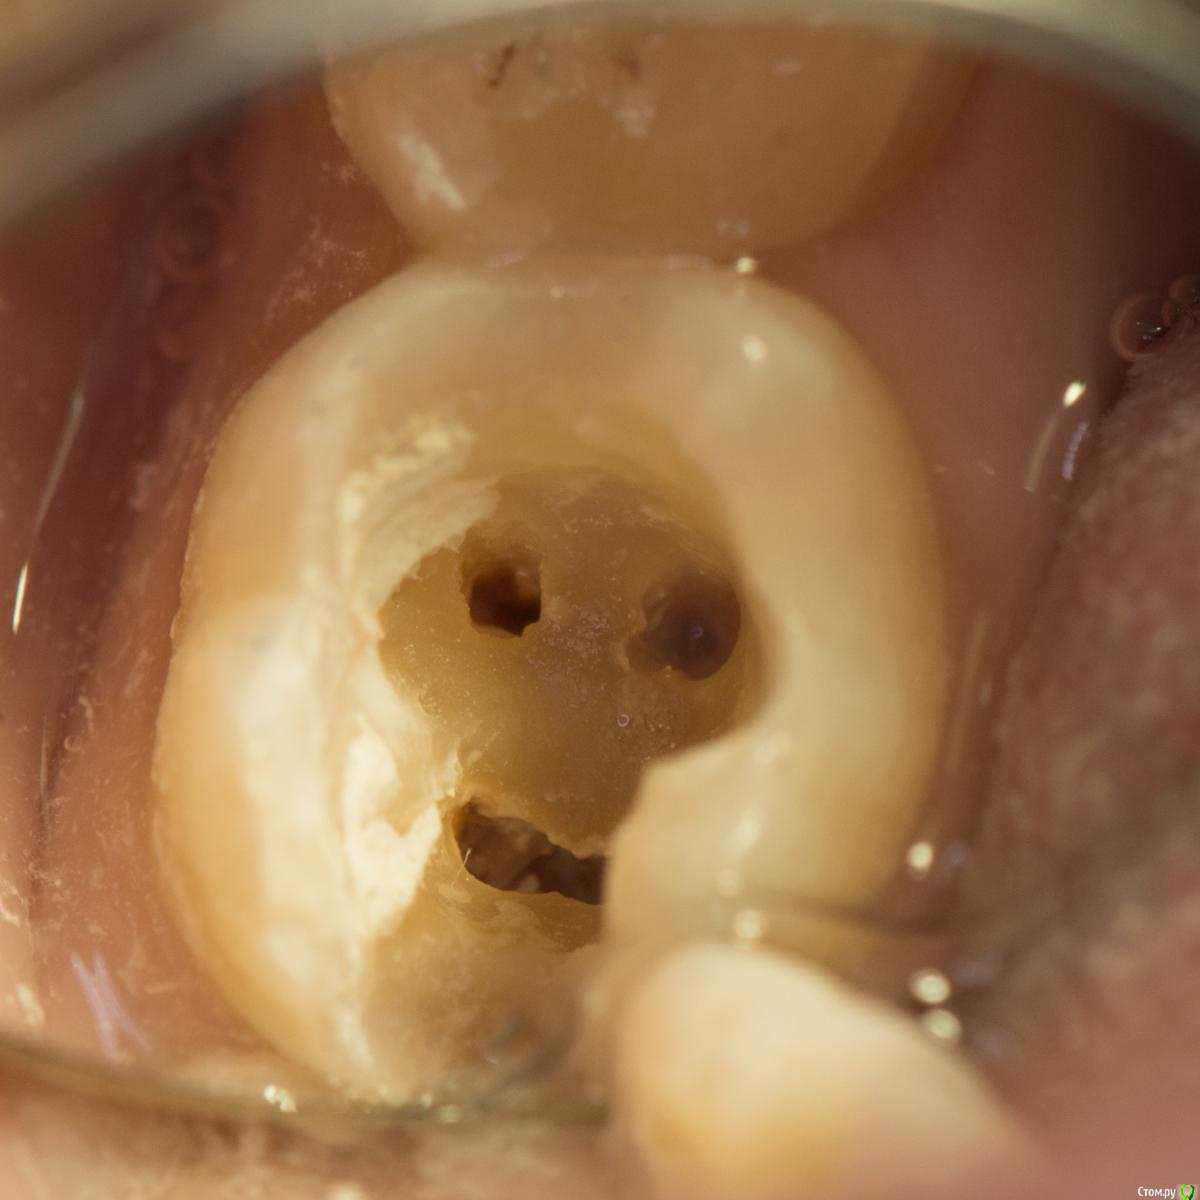

сирена Опубликовано 11 февраля, 2016 Поделиться Опубликовано 11 февраля, 2016 Автор мне неизвестен,нашла ВКонтакте.Изящно ) 13 Ссылка на комментарий

kriokov Опубликовано 11 февраля, 2016 Поделиться Опубликовано 11 февраля, 2016 Автор мне неизвестен,нашла ВКонтакте.Изящно )Рука б не поднялась пилить такие формы 3 Ссылка на комментарий

diesel87 Опубликовано 11 февраля, 2016 Поделиться Опубликовано 11 февраля, 2016 Рука б не поднялась пилить такие формы Такие формы нужно целиком!) 5 Ссылка на комментарий